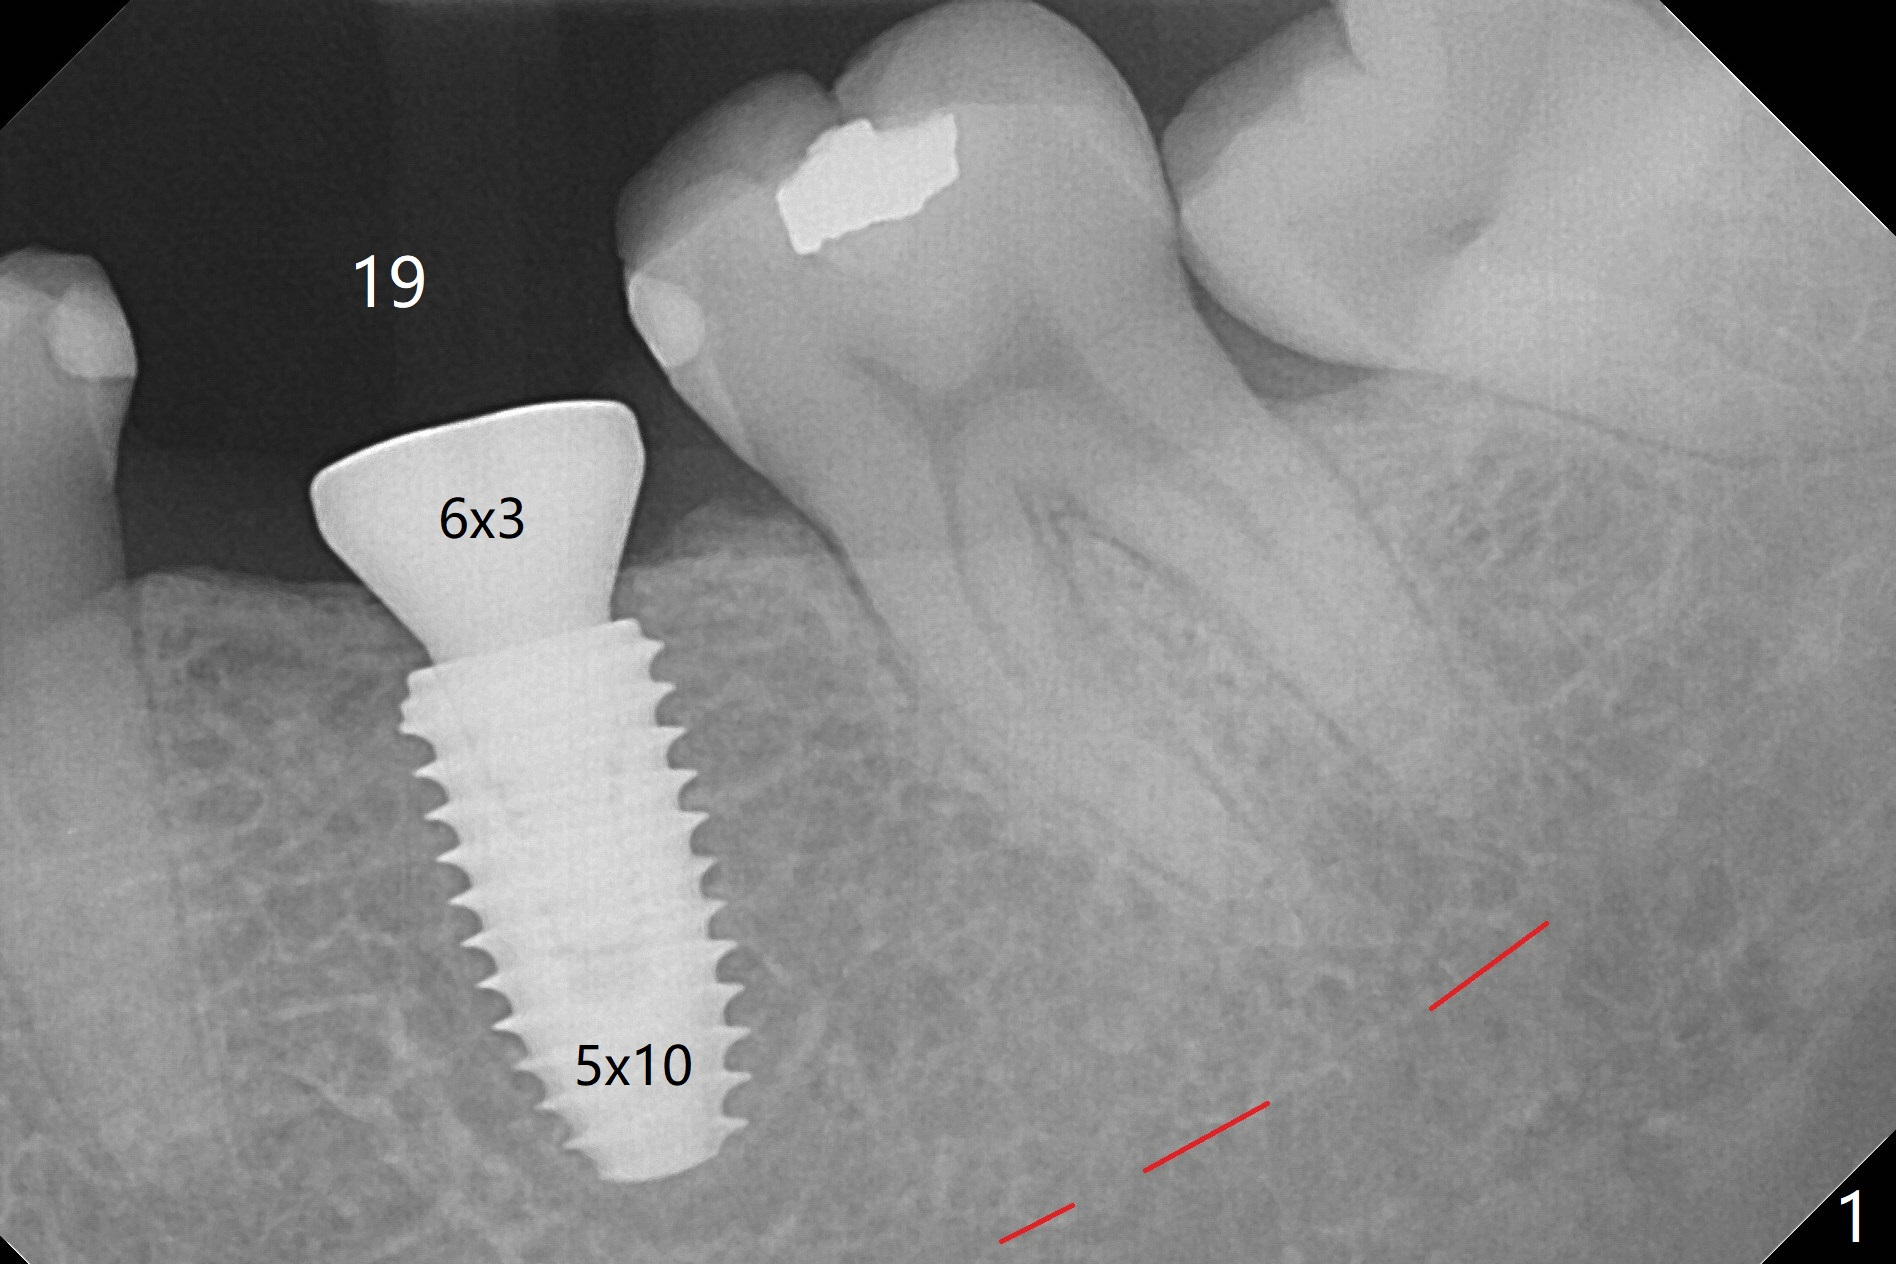

A 5x10 mm implant is intentionally placed distal at #19 using guided surgery (Fig.1). When it is osteointegrated, it will be used as an anchorage to upright the tooth #18 orthodontically. In fact the implant is mistakenly placed 1.5 mm deeper than planned without significant side effect (red dashed line: the superior border of the Inferior Alveolar Canal). The tooth #17 will be extracted before banding. The healing abutment dislodges (probably as related to deep placement of the implant) 20 days postop and is retightened. There is mild crestal bone loss 4 months postop (Fig.2). The tooth #17 is extracted with insertion of Osteogen Plug to prevent dry socket. A 5x4(2) mm cementation abutment will be placed with fabrication of a provisional with equi- or slightly subocclusal. Bands and brackets will be placed at #18-22. When open coil spring is placed between #18 and 19 with 18 ss wire, acrylic will be added to the occlusal surface of the provisional so that the tooth #18 is distalized without interference. The tooth #18 is distalized more than 1 month post placement of open coil spring (Fig.3). The tooth #18 is also lingually tilted (Fig.5), as compared to the contralateral side (Fig.4). After placement of 20 ss wire and longer coil spring, an elastic is placed between the lingual cleat of #18 and the buccal (lingual) button of #15 (Fig.5) to correct the lingual tilt. The tooth #18 is distalized ~ 1 mm shown by X-ray, although more clinically, 2.5 months post open coil spring (Fig.6). The bone density around the implant, particularly mesial, increases, as compared to Fig.2. The treatment finishes with normal overjet in the 2nd molars 11 months postop and 5 months post banding (Fig.7). It appears that the buccal groove of the lower 2nd molar (Fig.8 >) has been distalized to occlude with the mesiobuccal cusp of the upper 2nd molar (^). The width of the dense bone around the implant increases 14 months postop (3 months post cementation, Fig.9).